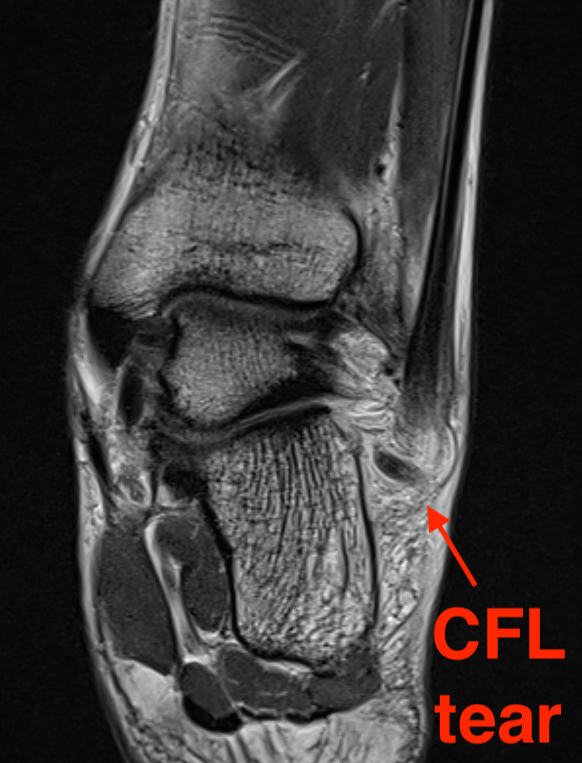

MRI

CFL tear